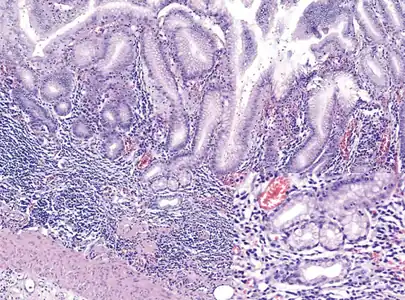

Histopathology of fundic mucosa with atrophy. H&E 10x; square 20x. Fundic-corporal gastric mucosa with extensive loss of gastric glands, partially replaced by pseudo-pyloric metaplasia.